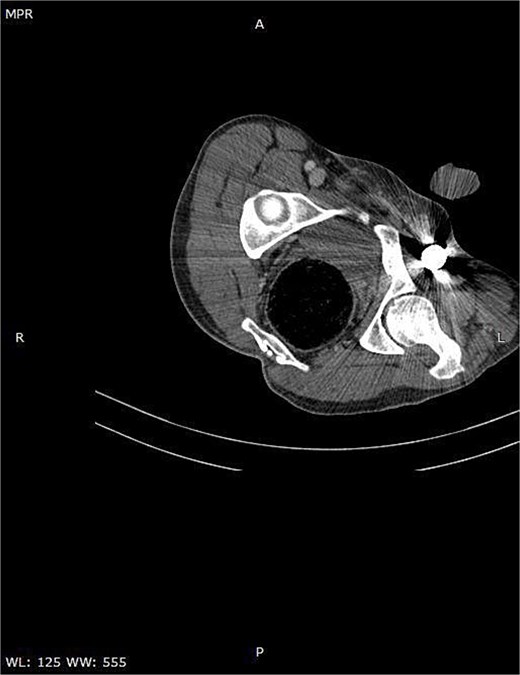

A CT scan of the pelvis, abdomen, and chest revealed the metal rod’s trajectory, penetrating the medial aspect of the left proximal thigh and traversing the left inguinal region lateral to the femoral vessels and nerve, with no evidence of vascular injury or hematoma (Figs 2 and 3). The rod continued through the abdominal wall in the subcutaneous plane without entering the peritoneal cavity, and no free fluid was detected (Fig. 4). It then extended through the left chest wall, associated with subcutaneous emphysema, but no intrathoracic injury was evident.

Axial CT image demonstrating the metallic rod positioned in close proximity to the femoral sheath without evidence of vascular injury.